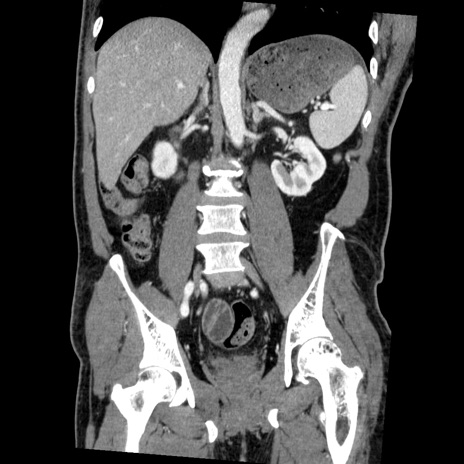

症例22(冠状断像)

【症例】50歳代男性

【主訴】腹痛

【現病歴】AVMからの被殻出血のため回復期リハ病棟入院中。 本日午後3時頃急に下腹部痛が出現した。

【既往歴】AVM、被殻出血、虫垂炎、高血圧

【身体所見】意識晴明、左半身不全麻痺、会話の理解は良好、36.5°C、腹部:膨隆、全体に板状硬、下腹部正中に圧痛点あり、反跳痛-、筋性防御不明、右下腹部にope scar

【データ】WBC 9400、CRP 0.06